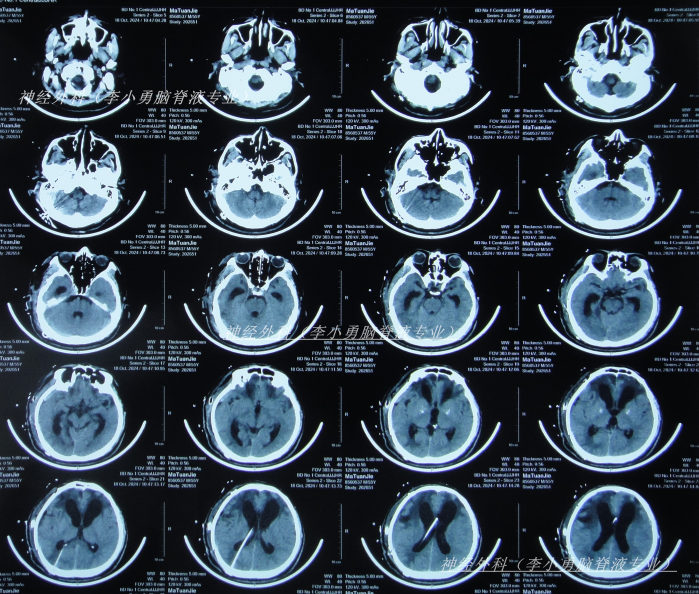

脑室腹腔分流术后22天即2024年10月11日,查头颅CT示脑室缩小(图-2)。

图-2:2024年10月11日头颅CT

脑室腹腔分流术后28天即2024年10月17日,进行了颅骨修补术(图-3)。

图-3:2024年10月18日头颅CT

颅骨修补术后5天即2024年10月22日(脑室腹腔分流术后33天),查头颅CT示颅骨修补术后状态(图-4)。

图-4:2024年10月22日头颅CT

颅骨修补术后10天即2024年10月27日(脑室腹腔分流术后38天),可以自行站立,搀扶下能走,查头颅CT(图-5)后转至某康复医院。

图-5:2024年10月27日头颅CT

因症状没有改善,决定到北京就诊,经过考虑在李小勇脑脊液专业和北京某三甲医院,选择了北京某三甲医院,2025年1月10日(颅骨修补术后85天即脑室腹腔分流术后113天),住入北京某三甲医院,查头颅CT(图-6)和腰穿检查后考虑颅内感染,给予抗感染治疗。

图-6:2025年1月10日头颅CT

保守治疗1周没有效果,于2025年1月18日(颅骨修补术后93天即脑室腹腔分流术后121天),再次选择了北京另一所三甲医院,查头颅CT(图-9)后急诊留观,行脑脊液检查提示人类疱疹病毒。

图-9:2025年1月18日头颅CT

该院治疗10天即2025年1月27日,查头颅CT示脑室进一步扩张(图-10)。

图-10:2025年1月27日头颅CT

入院当天查头颅CT示颅脑术后改变,脑室扩张,双侧额部硬膜下积液(图-12);胸部CT示两肺炎性病变,心包积液,双侧胸腔积液(图-13)。

图-12:2025年2月4日头颅CT

图-14:2025年2月4日术后头颅CT

住院治疗5天即2025年2月8日,查头颅CT示脑室有缩小(图-15)。

图-15:2025年2月8日头颅CT

图-17:2025年3月4日头颅CT

住院治疗1月零23天即2025年3月27日,查头颅CT和肺部(图-19)示感染大幅度好转。

图-19:2025年3月27日头颅肺部CT

继续治疗1月半脑脊液各项化验达标后于2025年6月3日,进行了脑室腹腔分流术(图-21)。

图-21:2025年6月4日头颅CT